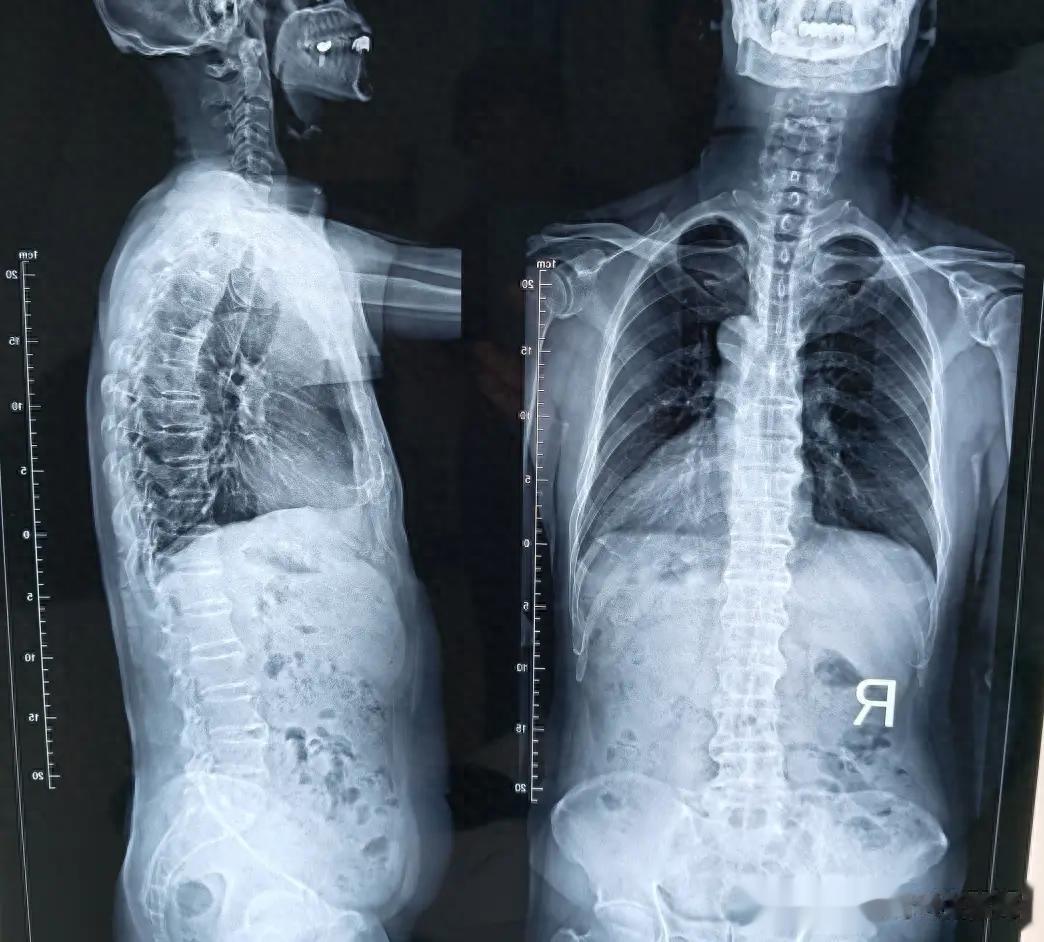

最终结果就是:脊柱从一根灵活的“链条”,逐渐变成一根僵硬的“骨棍”(医学上称为“竹节样变”)。

案例2:从“C形”回到“I形”的工程师

45岁的王工确诊时已发病15年,脊柱侧弯形成“C”形,穿衣服总有一边空荡荡。

现在他体态改善明显,虽然X光片上的弯曲还在,但他说:“最值的是,我终于能平躺着睡个整觉了。”

老中医心语:中晚期的治疗,目标不是追求X光片的完美,而是功能的恢复。 就像一棵长歪的树,我们不求它完全笔直,但能通过修剪让它继续向上生长、开花结果。